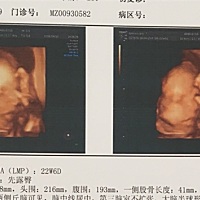

胎盘低咋办,能看出男女